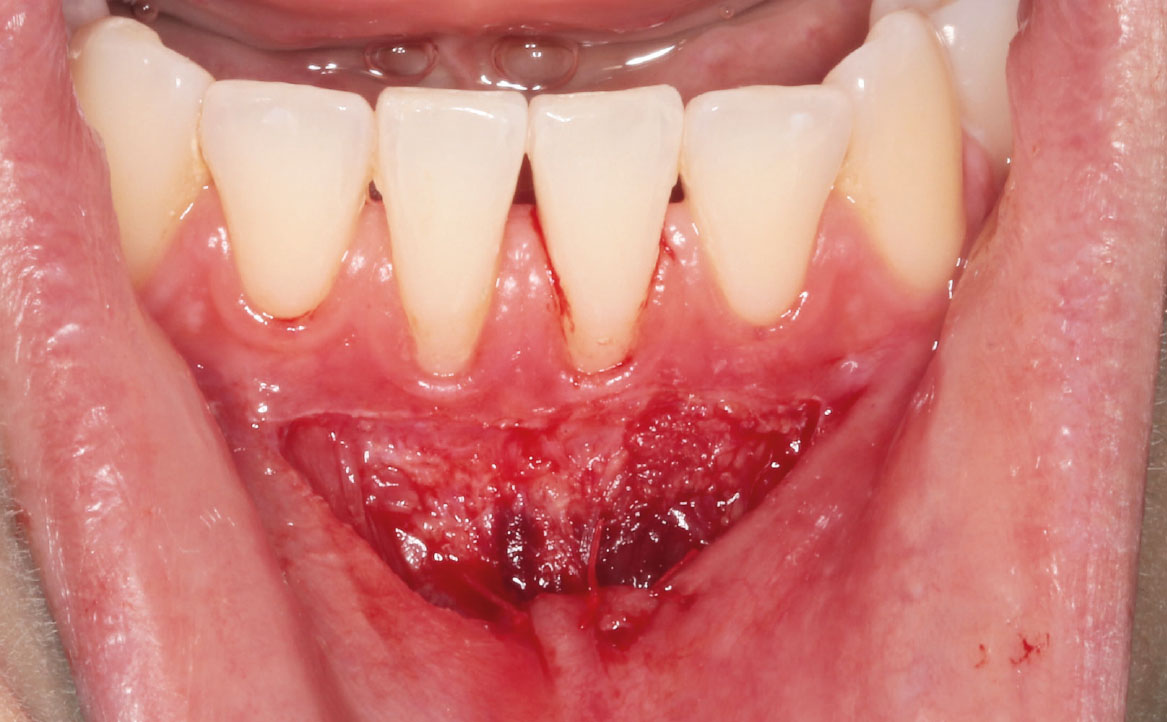

Previa anestesia loco-regionale plessica con lidocaina, è stata eseguita un’incisione parallela rispetto alla cresta alveolare e scollamento della mucosa mediante un laser neodymium yttrium aluminum garnet laser (Nd:YAG, 1064nm, 3.75W, 75Hz) (fig. 4-5).